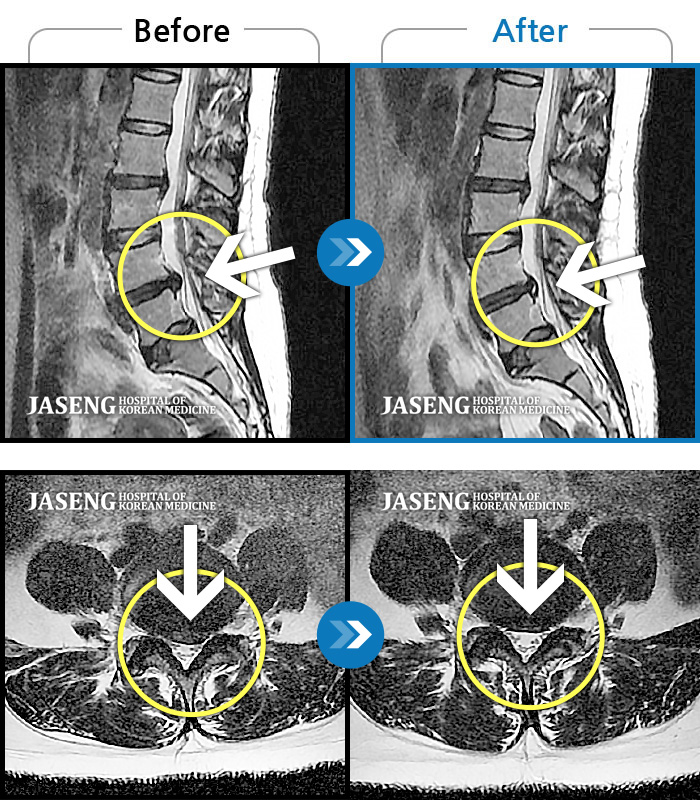

MRI 치료사례

처음 내원 시 양측 골반에서 좌측 대퇴, 소퇴 전면 통증 및 저림이 심해서 거동이 힘든 상태였습니다.